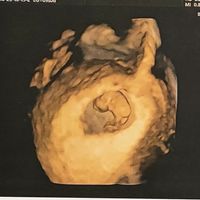

Hola! Me he animado a abrir el post y espero que poco a poco seamos muchas 🤰🏼. Yo vi mi positivo el pasado sábado y mi FPP es el 11 de Mayo. Todavía estoy de muy poquito y al ser primeriza total me...